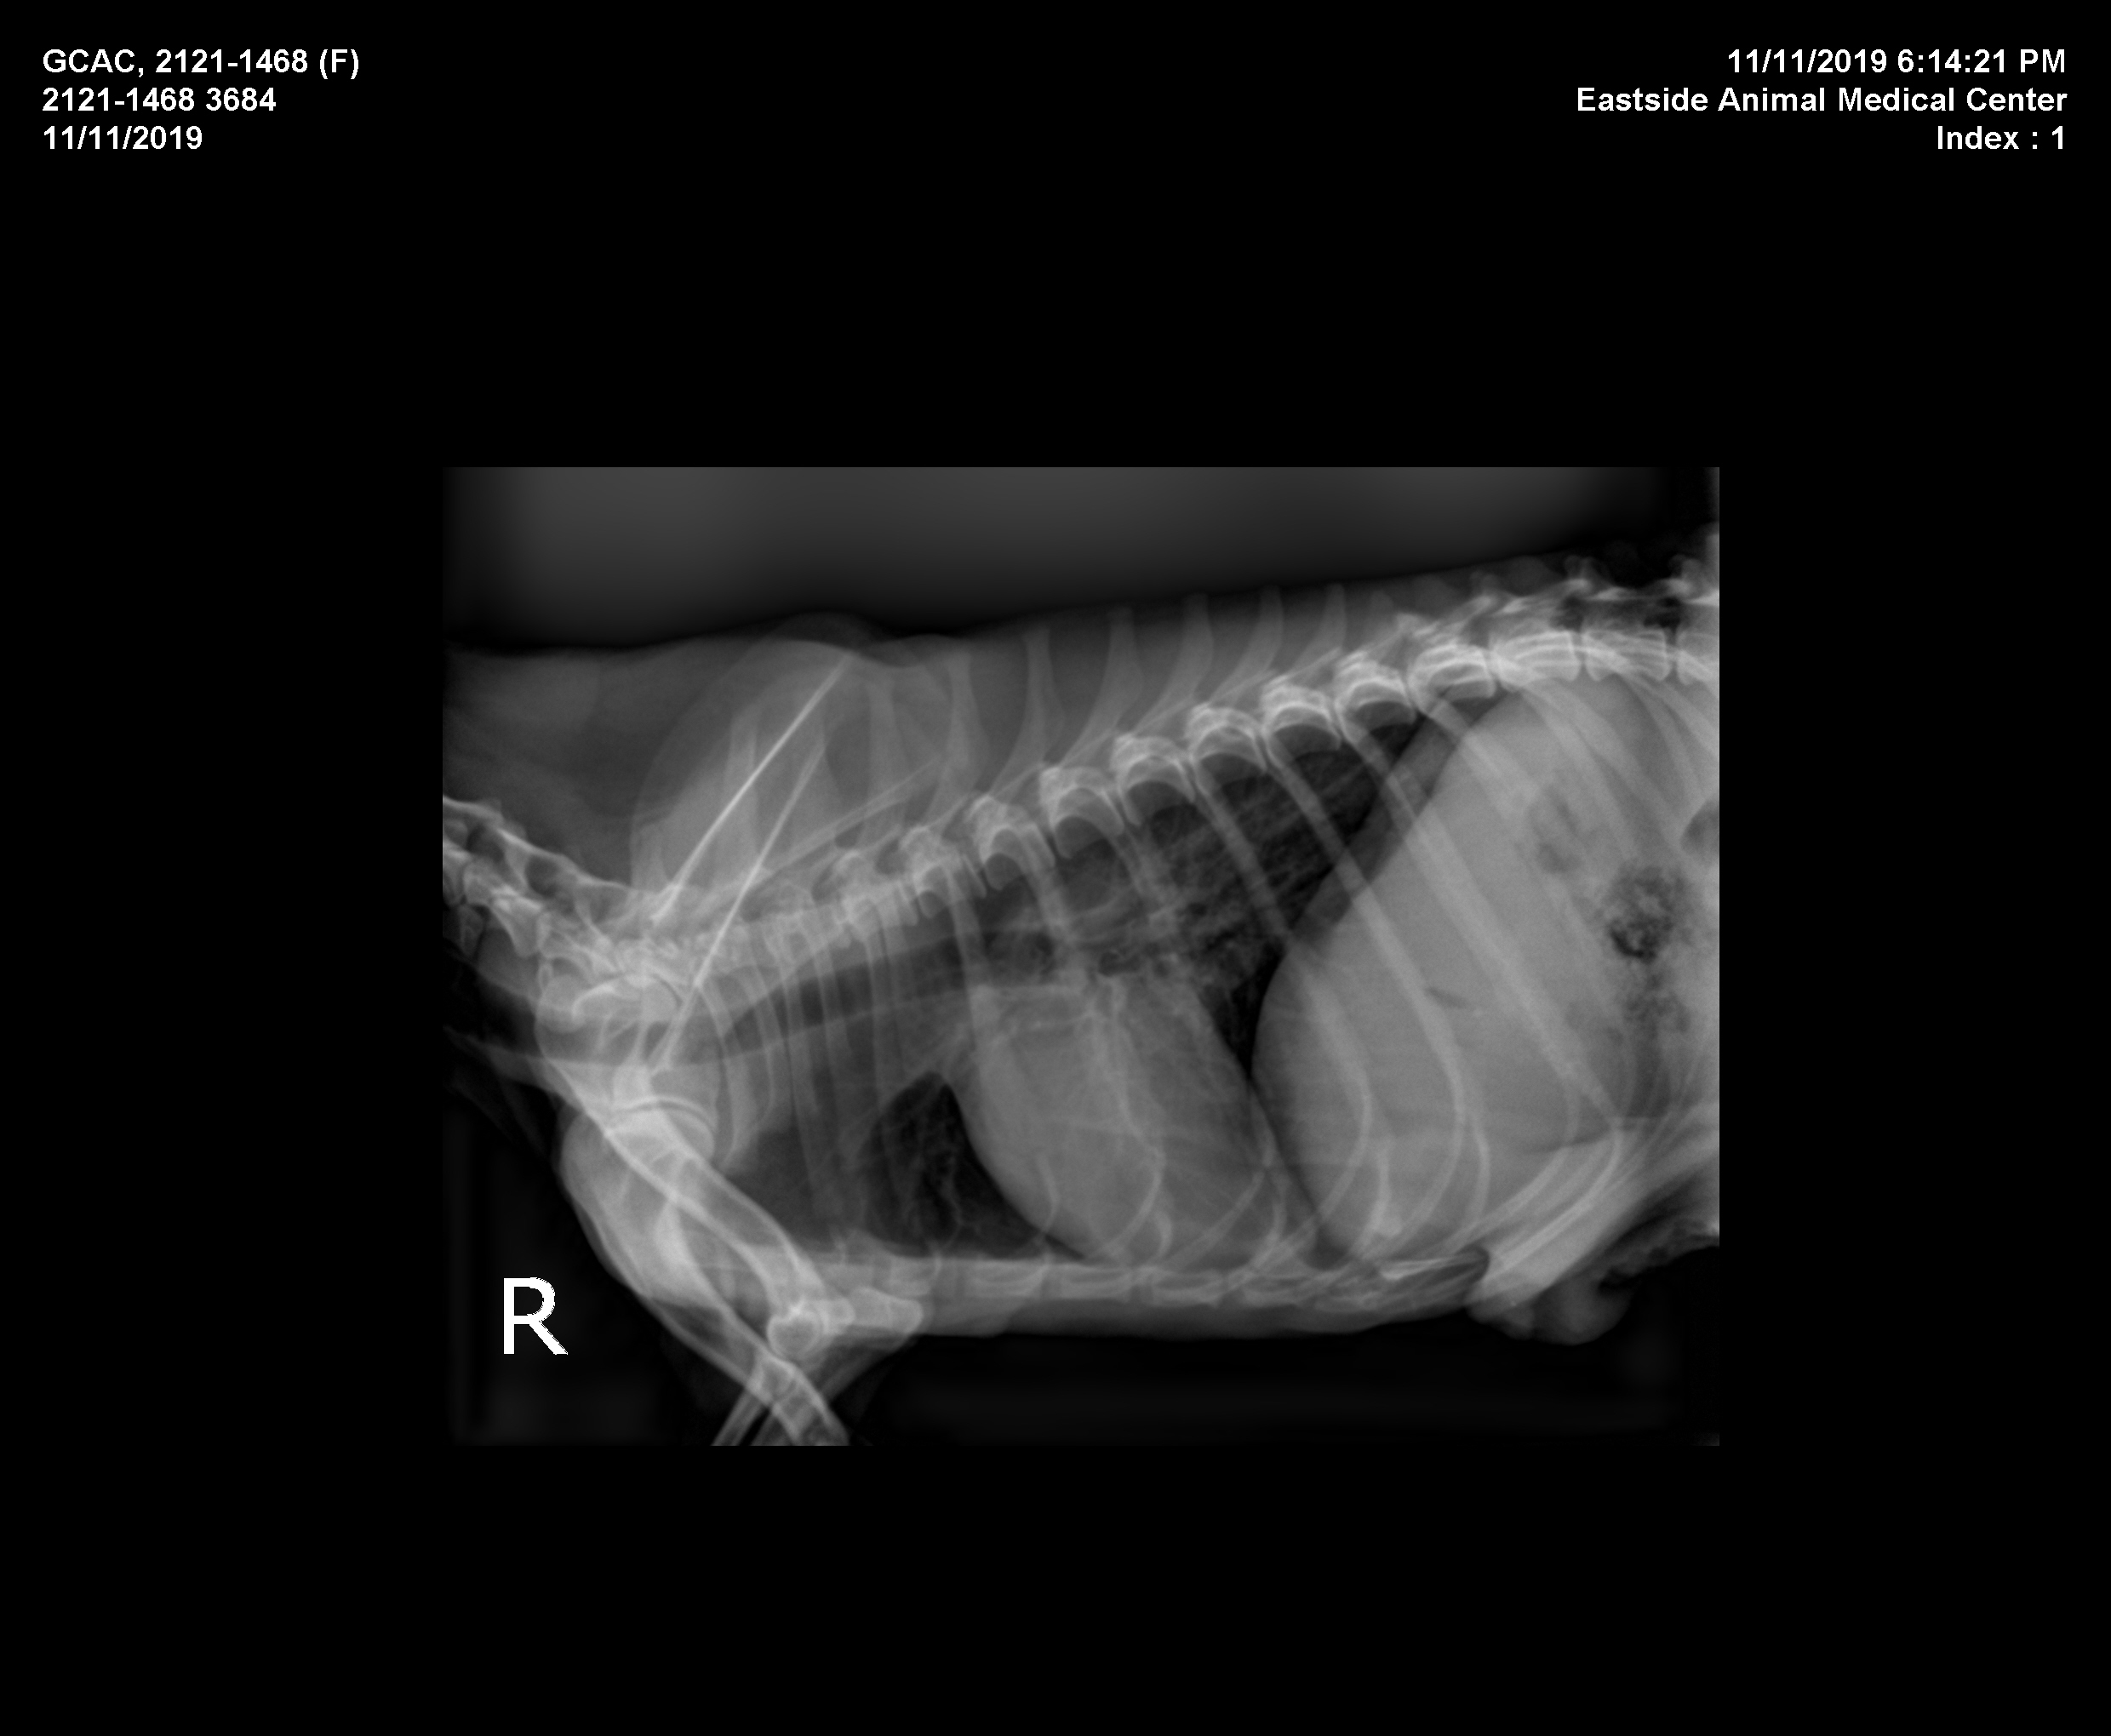

We are doing more x-rays and diagnostics to determine the value of more surgery for this adorable pup. We are still paying off her surgical and medical bills and have more coming in daily.  Please, Help Us, Help Her by DONATING.   For some reason, our Cancer Patients are the ones that get the least amount of funds. I am always personally having to pay off their bills.  Don't rule these pups out. They have each endured unimaginable hardship to be as sick as they are. Give them the same Gift you give all the others, the Gift of Life.